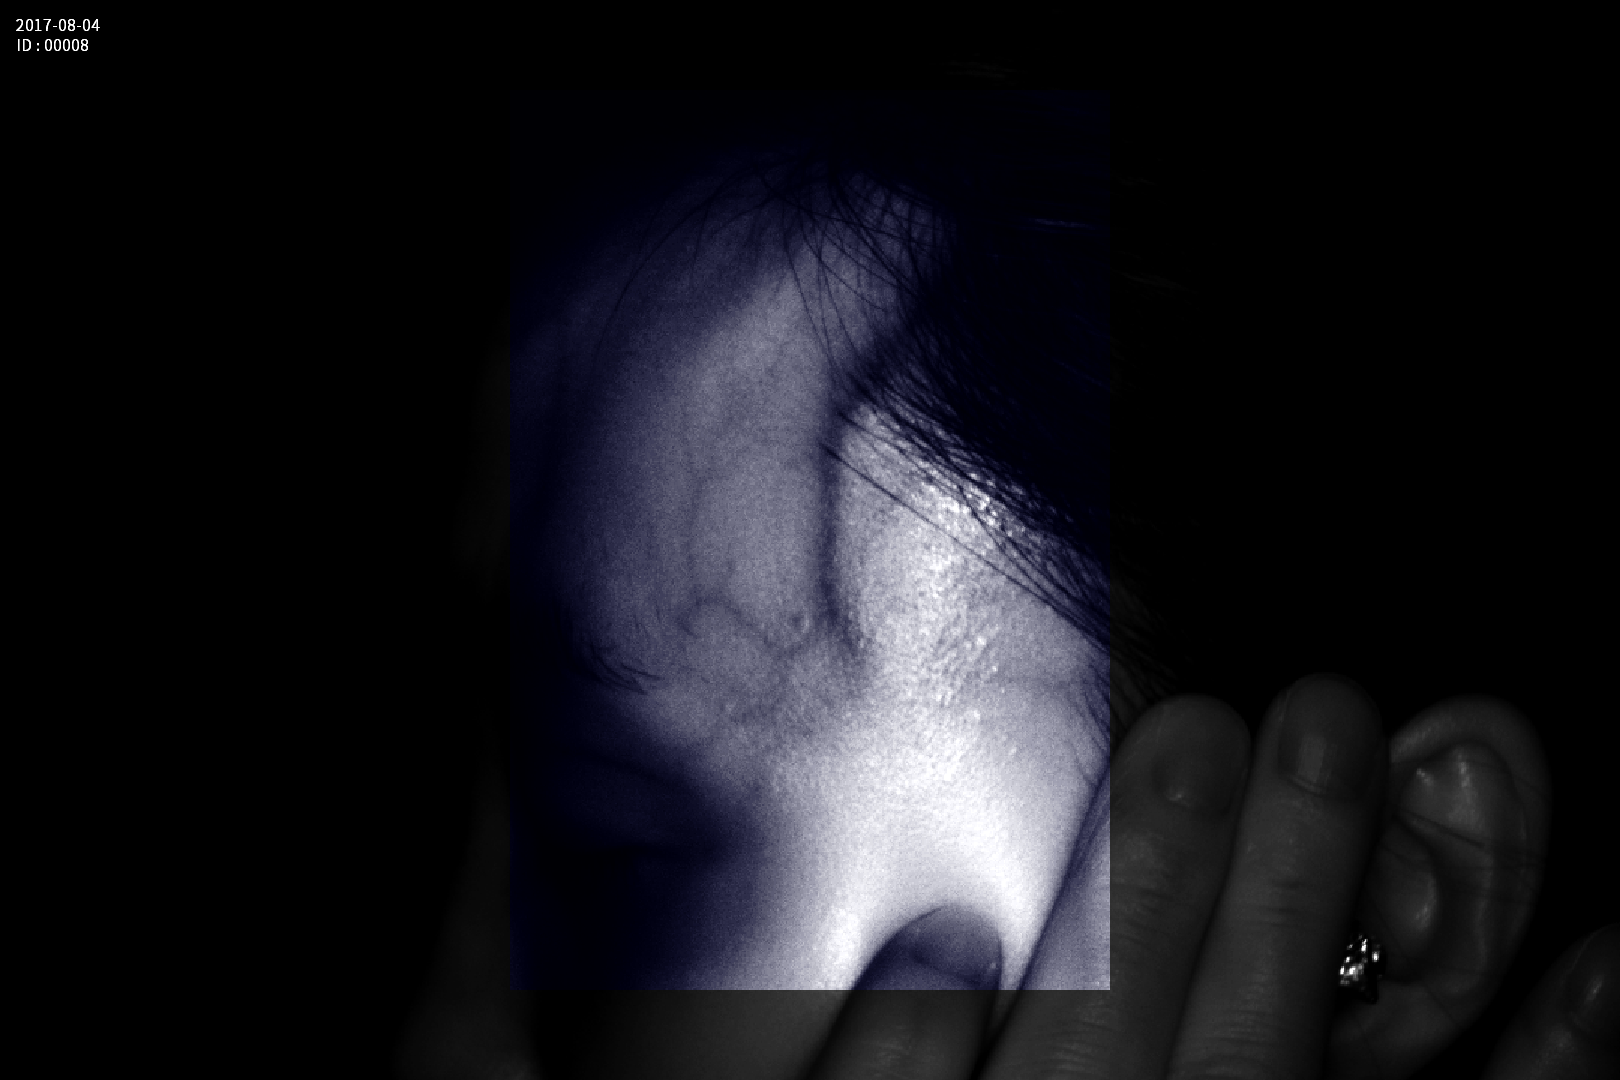

Grad mare de detecție a venelor greu vizibile până la 10 mm adâncime (inclusiv vene faciale)

Calitate înaltă a imaginii având o rezoluție de 1280 x 800 pixeli

Imaginea venelor este proiectată pe monitorul propriu în timp real si ajută la identificarea corectă și precisă

Multiple aplicații de vizualizare vene atât la sugari cât și la pacienții obezi sau în urgențe indiferent de tonul de culoare a pielii

- Camera de vizualizare cu tehnologie infrarosu